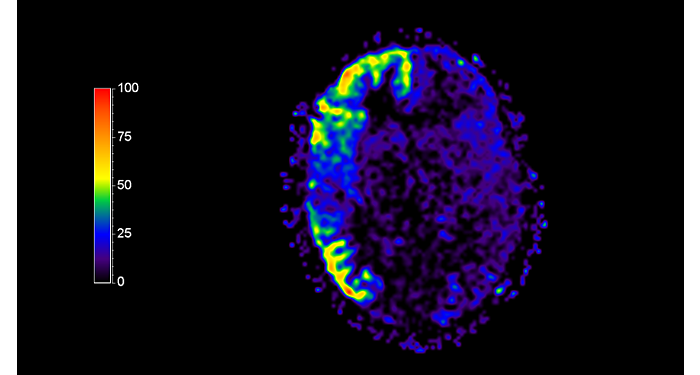

Imágenes de la IRM de campos oscuros de un paciente con VIH con vasculitis cerebral

Las imágenes de campos oscuros ayudaron a sugerir el diagnóstico y elegir el tratamiento.